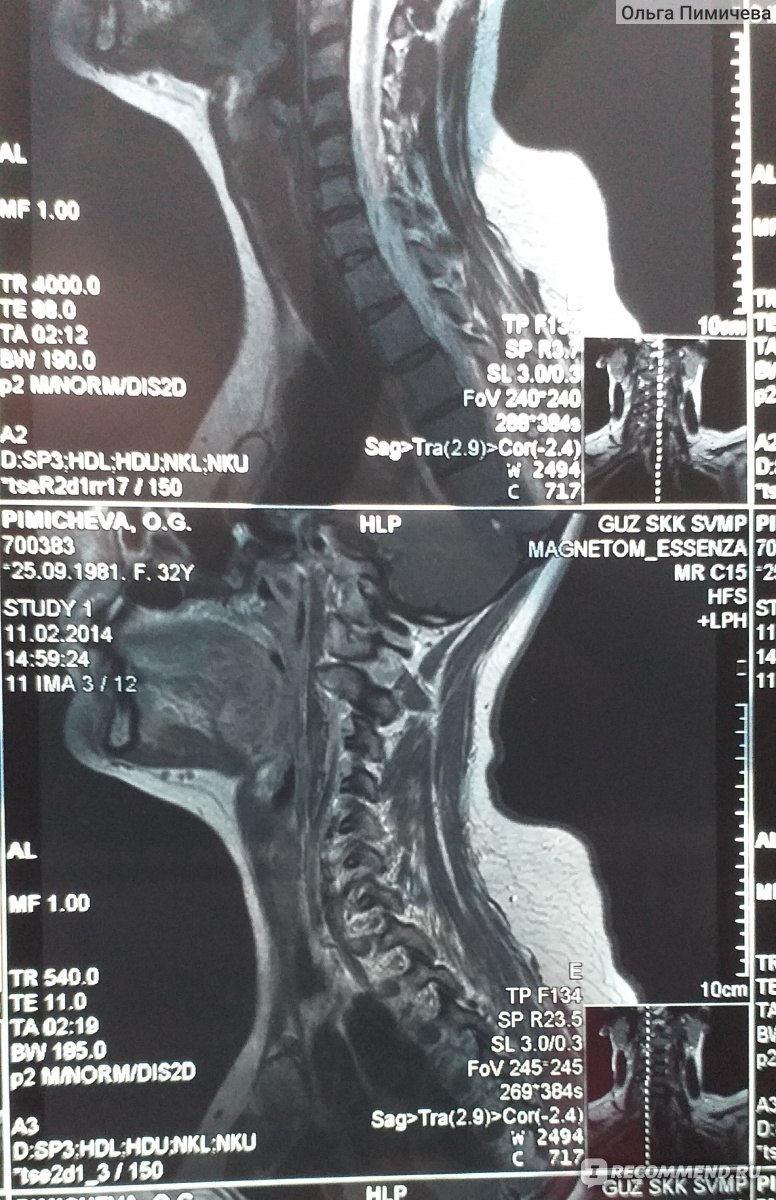

Отделы позвоночника для мрт схема фото и названия